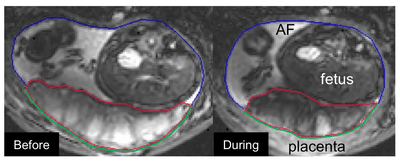

Advanced deep learning for medical MRI segmentation using U-Net and U-Net++ on placenta and brain tumor datasets.